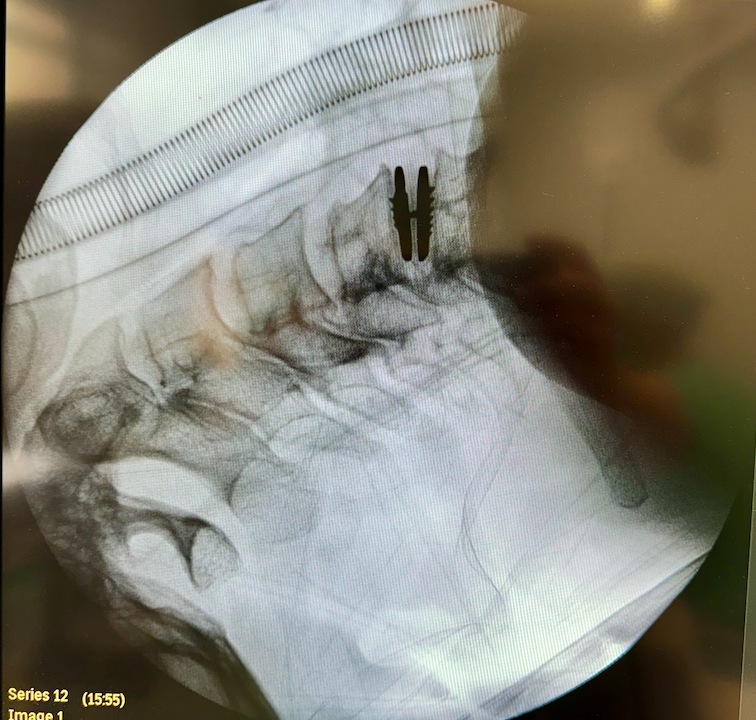

54 m. vyrui kakle implantuotas mobilusis diskas

Skundėsi įtampa kakle, nutirpusiais pirštais

Naujieji implantai sudaryti iš trijų dalių, dviejų specialaus metalų lydinio plokštelių ir iš polimero pagamintos šerdies, kurios, saveikaudamos tarpusavyje, geba išlaikyti įprastus stuburo segmento judesius.